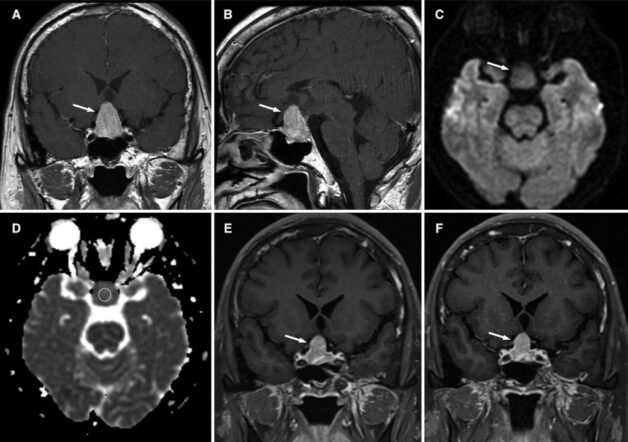

Hình ảnh chẩn đoán xác định u tuyến yên thông qua chụp MRI

– Đối với khối u tuyến yên lớn: Hình ảnh chụp xuất hiện khối tăng sinh xuất phát từ hố yên, phát triển chủ yếu lên phía trên. Đôi khi khối này sẽ xâm lấn sang hai bên ra xoang hang hoặc xuống dưới vào xoang bướm và phá hủy hết các cấu trúc tuyến yên. Các khối u này bắt thuốc cản quang mạnh, khá đồng nhất, đôi khi sẽ có xuất hiện nang trong u.

– Đối với khối tuyến yên nhỏ: Hình ảnh chụp cho thấy tổn thương xuất hiện bên trong tuyến yên, phát hiện được khi chụp động học tuyến yên có tiêm thuốc đối quang từ. Khối u thường đẩy lệch cuống tuyến yên sang bên đối diện. Những khối này thường bắt thuốc muộn hơn mô tuyến bình thường.